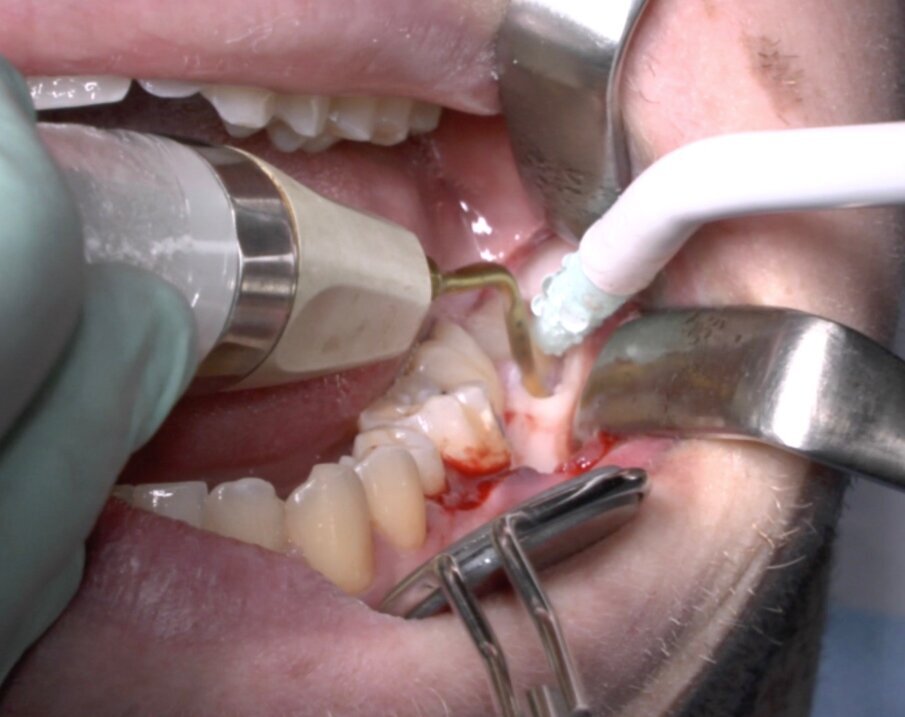

Fig. 5_Ostectomia con terminale piezoelettrico.

Fig. 6_Terminale piezoelettrico in azione.